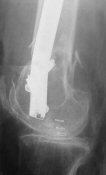

Attached are few examples from our Hospital:

A. Difficult reductions, even in retrograde nailing (my preference, easier control of "small" distal fragment) and it is much, much harder to do it anterograde (Alex, do you have one good case in your collection of anterograde nailing in very distal fractures - as you have suggested that I

should have done it in my previously posted case?

Malpositioning is much too common (recurvatum, varus - valgus).

B. Fixation loosening: distal cutting of the nail, non-unions do happen (cases attached).

Locking Plating has more distal screws than any nail, fixed angles and provides much better fixation, especially in osteoporotic bone.